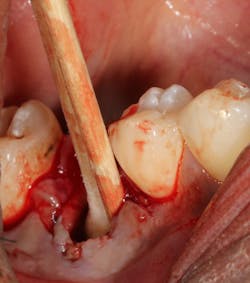

Failing implants that are afflicted with peri-implantitis usually are exposed to the same pathogens that affect natural teeth.7 These bacteria not only can coat an implant surface, but they also can be found in the surrounding peri-implant tissue. Complete removal of these bacteria via chemical detoxification of the residual implant socket and surrounding tissue can assist with removal of the pathogens (figure 3). Although both are effective, chemical modification with a neutral EDTA with a pH of 7.4 is a kinder alternative to tissue compared to 60% citric acid with a pH of 1. In addition, laser sterilization of the inflamed soft tissue surrounding the failed implant can help increase tissue tone during healing (figure 4).

Figure 3: Cotton pellets soaked with 60% citric acid used to detoxify an implant socket